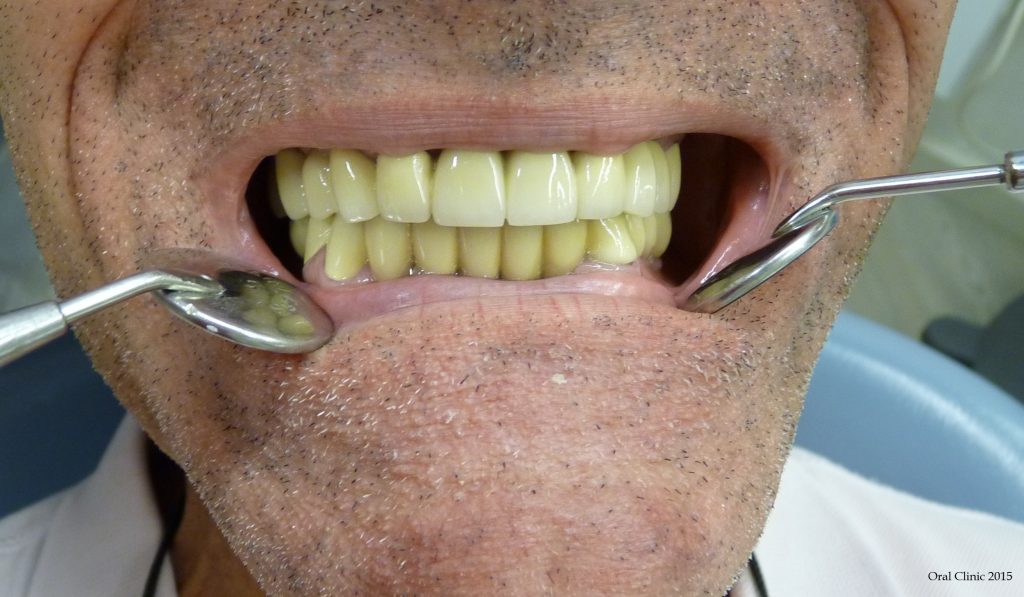

BRIDGE CERAMIQUE MIXTE DENTS NATURELLES ET IMPLANTS DENTAIRES

BRIDGE CERAMIQUE MIXTE DENTS NATURELLES ET IMPLANTS. CONTROL 3 ANS.   Pose d’un bridge ceramo metallique de 12 dents sur des implants dentaires et des dents naturelles. Au niveau des implants, intégration tissulaire parfaite grâce aux connexions implantaires supra-gingivale.   Chirurgien: Dr. Thierry Hascoet Prosthodonte: Dra. Yanira Peña Laboratoire: SIVP Barcelone